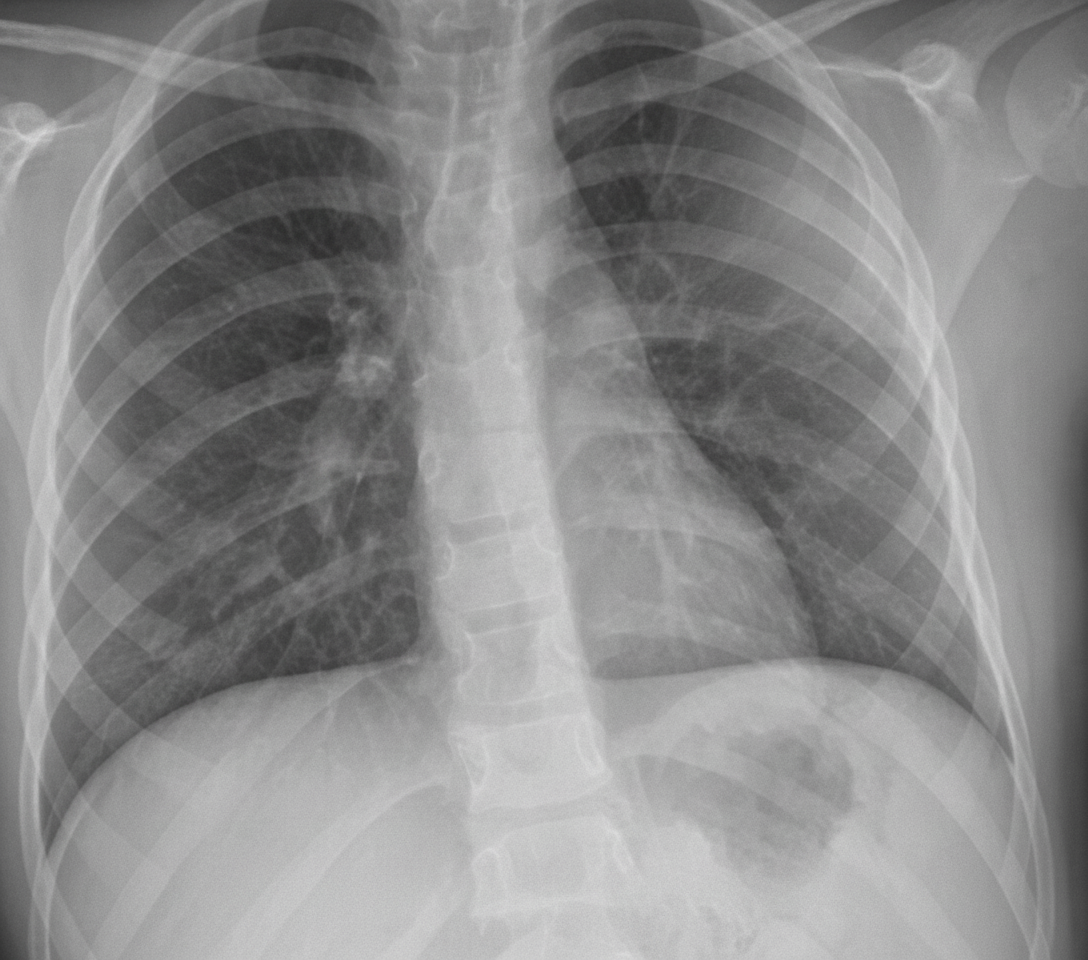

A 54-year-old non-smoking male presents with a flulike illness. Initially treated symptomatically, he returns two days later still feeling unwell. His primary physician prescribes a macrolide along with symptomatic treatment. After five days, the patient reports persistent fever, increasing fatigue, weakness, and cough. He also experiences pain and limited motion in his right wrist, and left groin pain with difficulty ambulating. On physical exam, vital signs include pulse 110 bpm, temperature 102°F, respirations 24/min, and blood pressure 100/68 mm Hg. He appears weak and has lost 8 lb in 10 days. Lung examination reveals egophony and E to A changes in the left anterior and posterior fields. Physical findings include swelling with skin sloughing on the right wrist and tenderness with limited movement in the left groin. Laboratory data shows Hb 11 g/dL, Hct 33%, WBCs 16,000/uL with 90% neutrophils, BUN 42 mg/dL, creatinine 1.1 mg/dL, sodium 142 mEq/L, and potassium 3.4 mEq/L. Arterial blood gases on room air are: pH 7.45, PCO2 34 mm Hg, PO2 65 mm Hg. A chest X-ray is provided. Associated findings may include all of the following except?

Explanation: ***Reye syndrome*** - **Reye syndrome** is associated with **aspirin use** in children during **viral infections** and involves mitochondrial dysfunction, not bacterial septicemia. - This condition is completely **unrelated** to **Staphylococcus aureus bacteremia** and would not occur as a complication of bacterial sepsis. *Septic arthritis* - The patient's **right wrist swelling** with skin sloughing and **left groin pain** with limited movement are classic signs of **septic arthritis**. - **S. aureus bacteremia** commonly causes **hematogenous seeding** of joints, leading to septic arthritis in multiple locations. *Endocarditis* - **S. aureus** is a leading cause of **acute endocarditis**, particularly in patients with bacteremia and systemic illness. - The patient's **persistent fever**, **hemodynamic instability** (BP 100/68), and systemic toxicity are consistent with possible endocarditic complications. *Brain abscess* - **Hematogenous spread** of S. aureus can lead to **CNS complications** including brain abscess formation. - The patient's **altered mental status** (weakness, fatigue) and systemic S. aureus infection put him at risk for this serious complication.